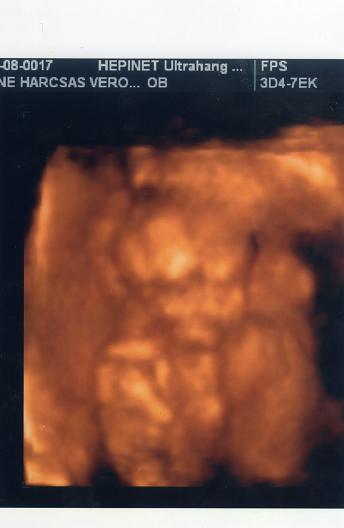

Hát én nem voltam oda meg vissza az expós 4d-ért. A kép meg maga az uhu az jó volt csak 6 perc alatt lezavarta a srác plusz kérdeztem a nemét és azt mondta hogy ekkor még nem látni pedig totáll neoplánba lehetett látni mert előről volt. Csak az ürge nem akarta azt nézni hanem mindig az arcát akarta. Én meg nem azt akartam na és nem értette meg. Így még jó hogy nem mondtam le a genesiseset mert elmegyek kedden oda is. Ott legalább bő fél óra lesz. Nem is kértem dvd-t róla. De azért lassan de mozgott bár ő is mondta hogy nem éppen aktív gyerek. Remélem ebből nem lesz bajom.

itt a kép